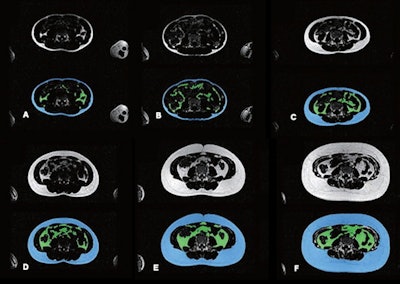

Researchers led by Dr. Tong Wu found that their model could successfully perform segmentation for subcutaneous adipose tissue (SAT) and visceral adipose tissue (VAT) when assessing fat distribution on MRI, along with ties between such distribution and clinical outcomes.

They trained, validated, and tested the model, a competitive dense fully convolutional network (2D-CDFNet), on data from participants in the Generation R Study. This prospective population-based cohort study in Rotterdam included 2,989 children with an average age of 13.5 years. The participants underwent investigational whole-body Dixon MRI after reaching age 13 years, during the study's follow-up phase. The model was trained to segment abdominal SAT and VAT using Dixon-based MRI.

The researchers found that for the test dataset, the Dice similarity coefficient and volumetric similarity were 0.94 and 0.98 for SAT, respectively. For VAT, these measures were 0.85 and 0.92, respectively. These results indicate that the model demonstrated strong quantitative performance.